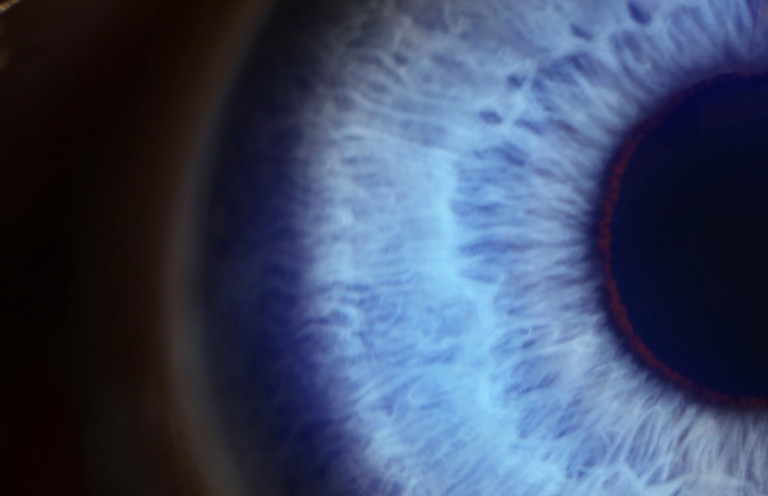

Figure 3. A case of left superior segmental optic nerve hypoplasia (SSONH). Note the average size of the optic disc with a thin and pale superior neuroretinal rim (white arrow), with reduced RNFL reflectivity in the superior and superonasal peripapillary region (green star). There is a reduction in capillary perfusion in the superior, superonasal and nasal peripapillary region on OCT angiography (yellow stars). There is a significant reduction in superonasal, superior and superotemporal RNFL thicknesses and GC-IPL thicknesses on OCT. 30-2 visual fields testing shows a dense inferior arcuate defect extending from the blind spot, also with superior extension of the blind spot.

There are four fundoscopic features that are typical of SSONH, although their presence has been reported as variable within affected eyes.6 SSONH may be unilateral or bilateral and is ubiquitously characterised by thin superior and superonasal neuroretinal rims with markedly reduced superior RNFL reflectivity.

The presence of associated superior disc pallor varies, being reported in 30% of cases. A superior entrance to the central retinal artery is noted in 60–65% of cases and a superior peripapillary halo (superior or partial ‘double ring’ sign) documented in 60–65% of cases.5-9All structural changes are localised to the superior portion of the optic nerve head, as illustrated by Figure 3.